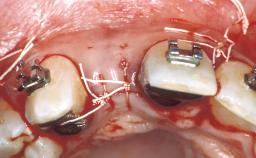

ITI Curriculum FL: Patient Assessment Case 10

Example intended for case-based discussion regarding patient assessment, diagnosis and determination of risk and complexity.